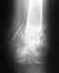

Есть два способа лечения деформирующего артроза суставов. Первый - консервативное лечение: витамины группы В, диклофенак, структум, трентал, никошпан (никотиновая кислота), грязи (парафин), электрофорез анальгина, фонофорез гидрокортизона,ДДТ, массаж, ограничение физических нагрузок и длительное пребывание на ногах. Второй - опреативное лечение: артродез подтаранного сустава. Данная операция ничем не грозит. Для фиксации таранной и пяточной костей применяется аппарат Илизарова. С временем оперативного лечения нужно определится самому.